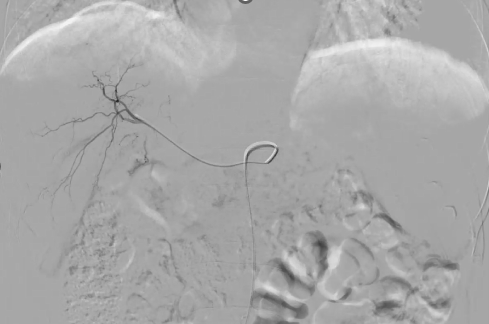

图5 行肝动脉置管术

2025-03-07至2025-03-28,行第3-4程肝动脉置管术,术后动脉给予FOLFOX+阿得贝利单抗1200mg,静脉给予贝伐珠单抗800mg